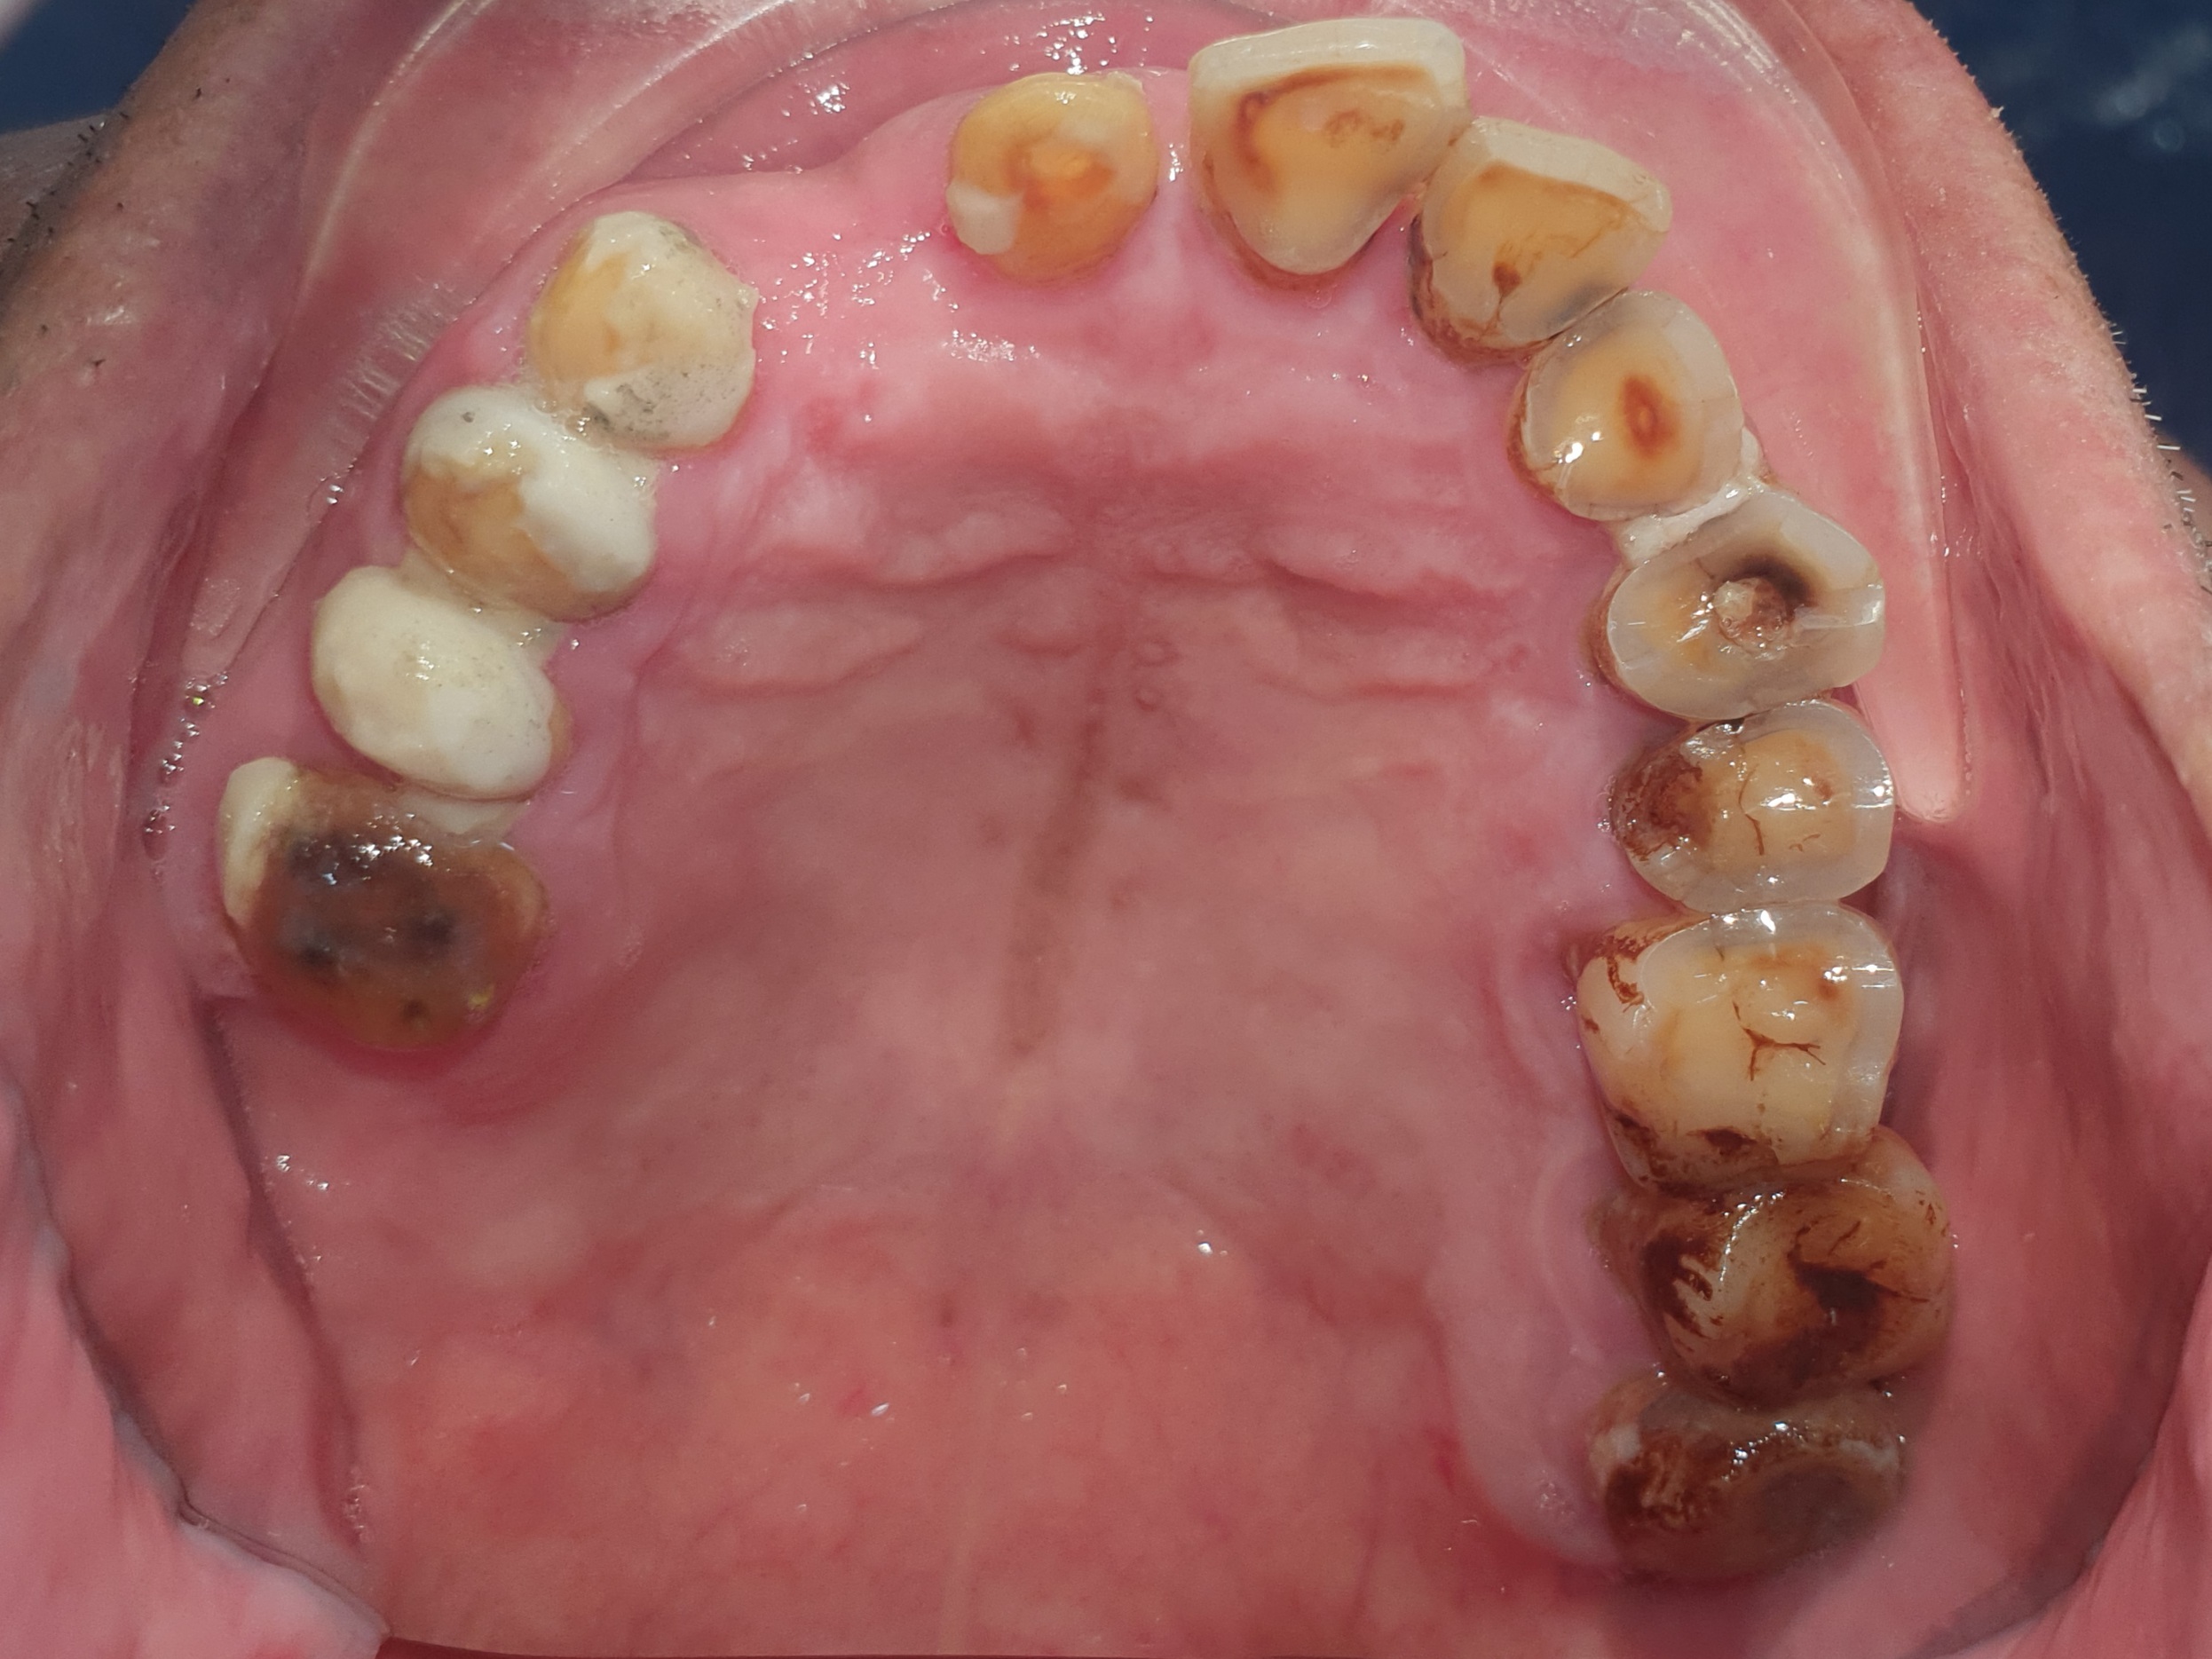

👉Qua thăm khám thấy:

– Bị mất kích thước dọc, cắn sâu. Khớp cắn rất nhạy cảm với thay đổi, dù là rất nhỏ.

– Răng sứ hiện tại quá to, và thô, làm dính liền tất cả các răng sứ với nhau, rất khó vệ sinh, dẫn đến viêm nướu nặng.

– Răng thật còn lại thì mòn cổ nặng, có răng nhiễm trùng cần điều trị tủy

-….

Tình trạng răng ban đầu

Hình ảnh răng hàm trên và dưới